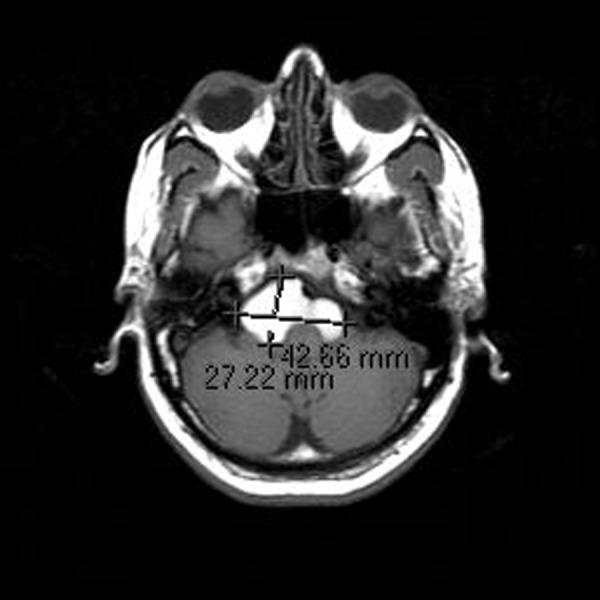

We present a rare, histologically proven case of a large lobulated intracranial neurenteric cyst measuring 4.2 centimeters in the maximal transverse dimension and involving bilateral cerebellopontine angle cisterns. We also present a review of the literature on this uncommon finding.

我们报告1例罕见的、经组织学证实的颅内分叶状神经肠囊肿,最大横径为4.2厘米,累及双侧小脑脑桥角池。我们还对关于这一罕见发现的文献进行了综述。